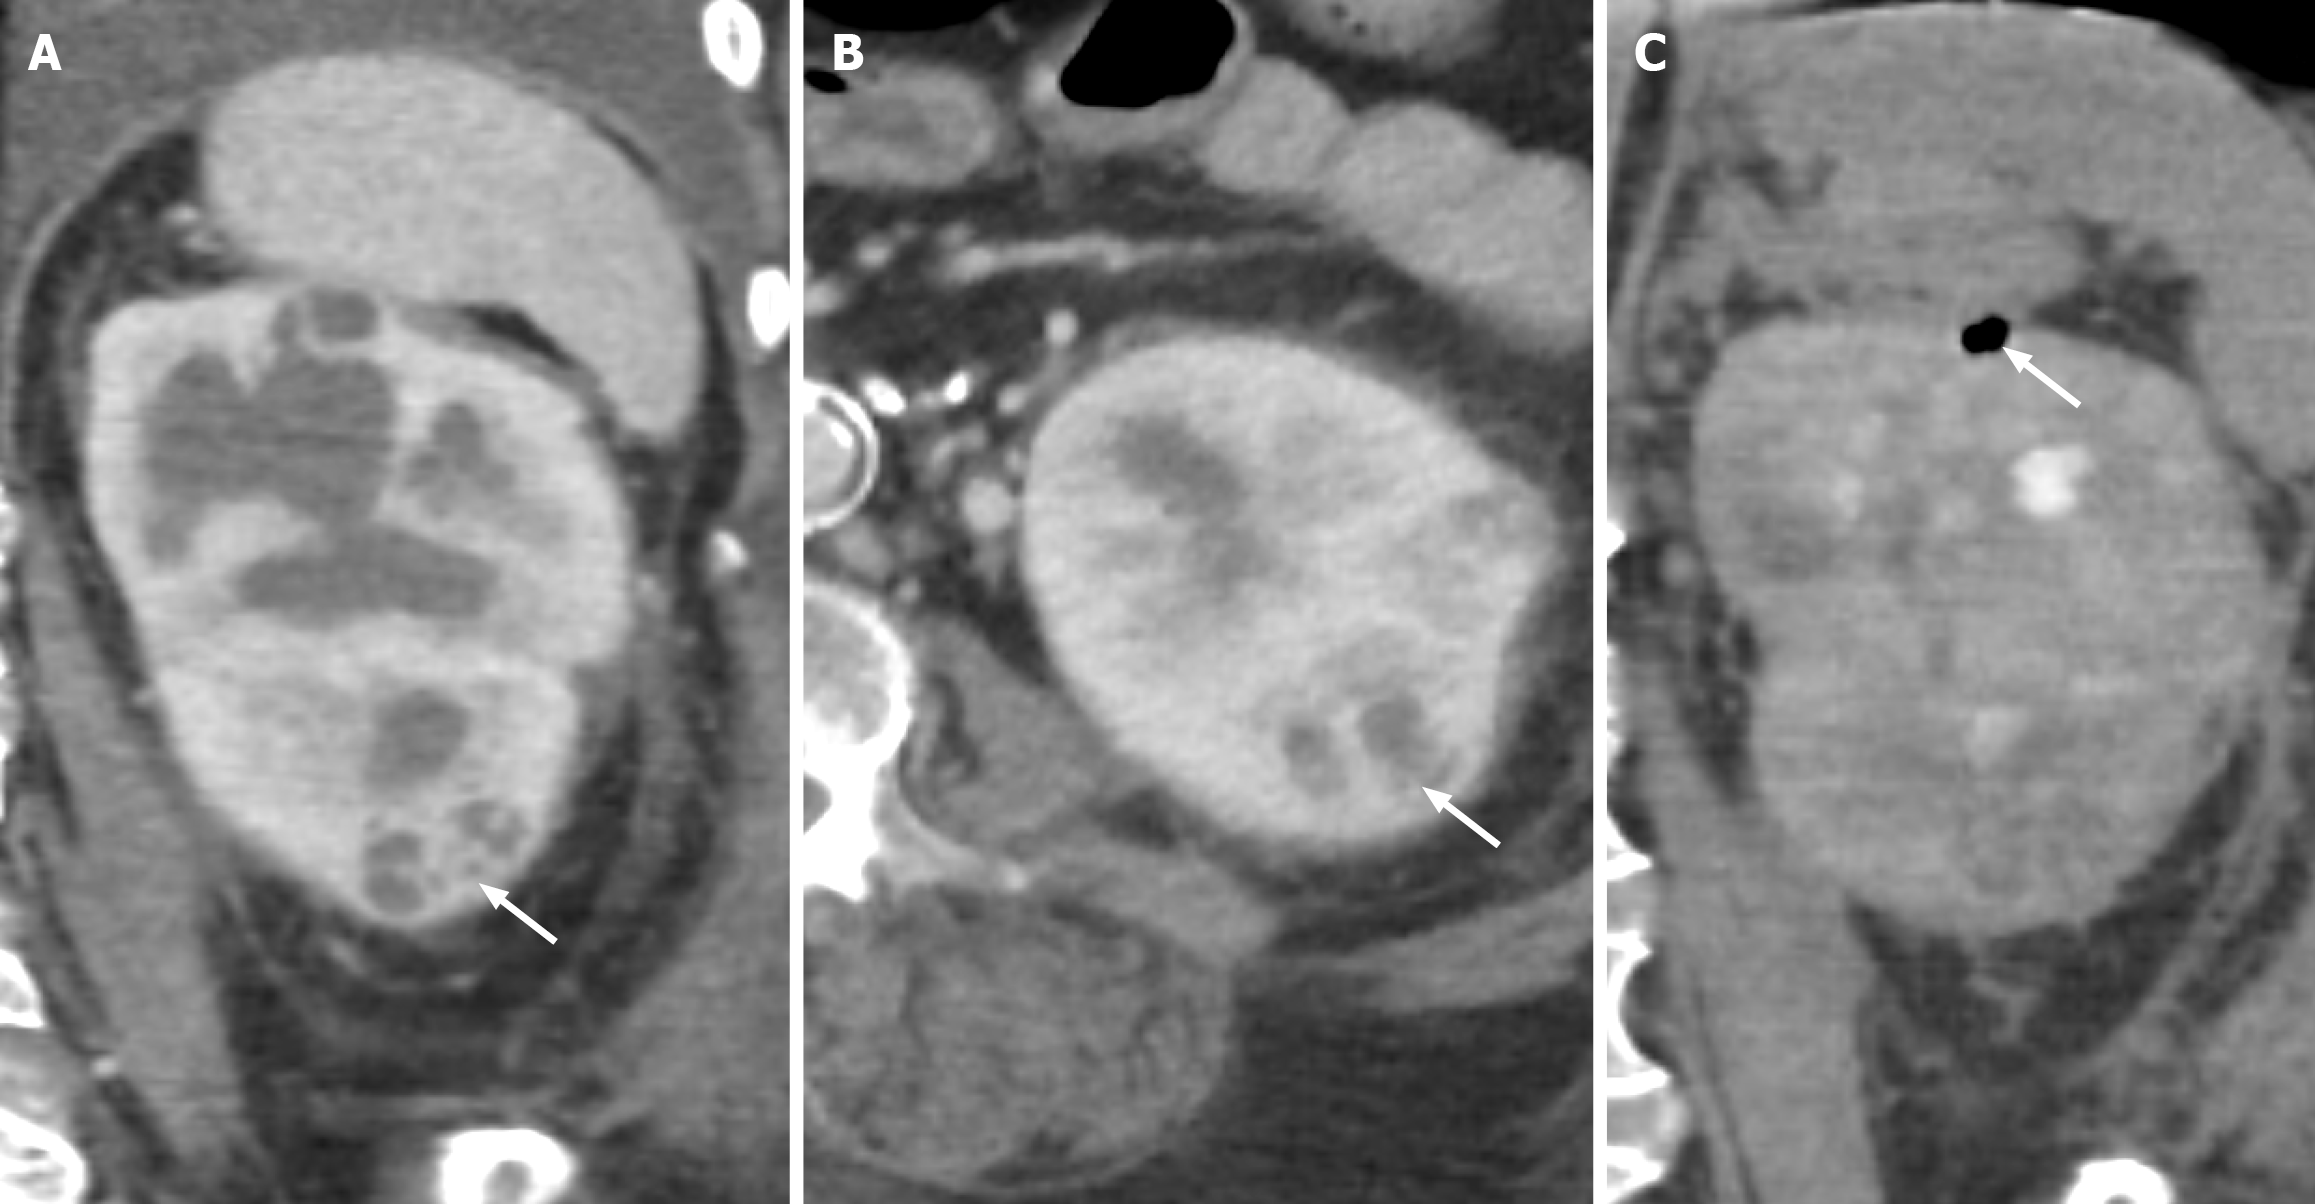

Figure 4 Grade IV renal injury.

A: Axial computed tomography of the abdomen in corticomedullary phase demonstrating renal hilar injury with diffuse hypoattenuating fluid collection in the hilum, concerning for collecting system involvement (white arrow); B: On delayed phase imaging, note the contrast extravasation from the renal collecting system into the hypoattenuating collection consistent with urine extravasation (white arrow). These findings correspond to grade IV renal injury.